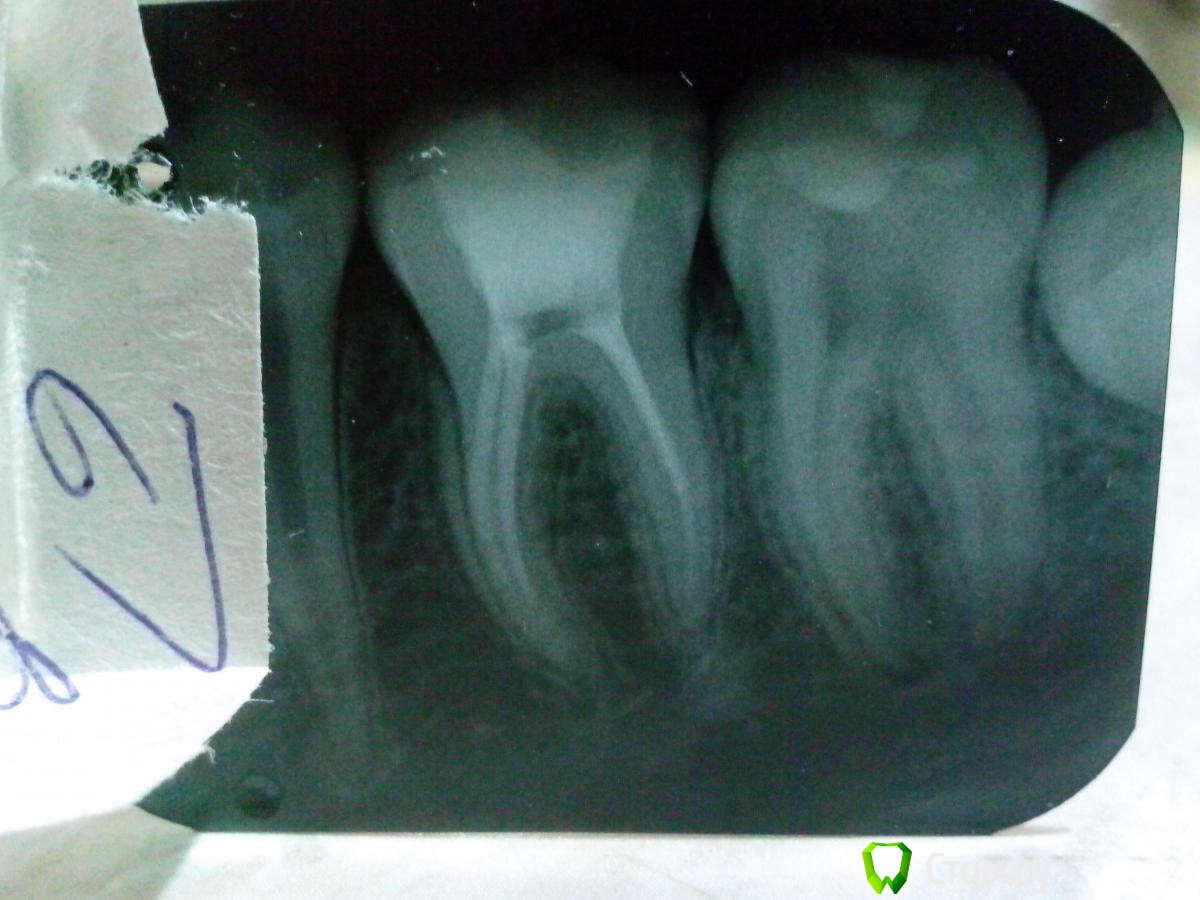

Olga25 Опубликовано 28 ноября, 2013 Автор Поделиться Опубликовано 28 ноября, 2013 Вот снимок подростка с запломбированными каналами.Сегодня приходил.Перкуссия болезн,говорит что кусать на него больно,но в общем не жалуется.Я предложила полоскания содой, понаблюдать.Конечно же я понимаю что нужно все исправить ,но в каналы опять не хочется лесть-паста уже застыла.Когда пломбирую гуттаперчей каналы получаются аккуратнее,но в этом случае не было их под рукой и я решила обойтись одной пастой.Больше так не буду.Как быть ?Промываю каналы эндоиглой хлоргексидином.Все обязательно прочитаю.Может еще кто знает полезную литературу.Сбросьте ссылки. Ссылка на комментарий

АнтонТЛТ Опубликовано 28 ноября, 2013 Поделиться Опубликовано 28 ноября, 2013 Согласна, но на курсах много информации о термафилах и эндомоторах ,а мне еще рано работать с этим.Хорошая штука для ирригации.Какими материалами вы пользуетесь? Как ведет себя ЦОЭ в каналах.Боюсь за этот зуб.Не знаю как быть.Вы заметили что там 2 дистальных корня? 1 Ссылка на комментарий

Kivilgar Опубликовано 28 ноября, 2013 Поделиться Опубликовано 28 ноября, 2013 Вы заметили что там 2 дистальных корня?+1. Опередил. Не получилась интрига. Ссылка на комментарий